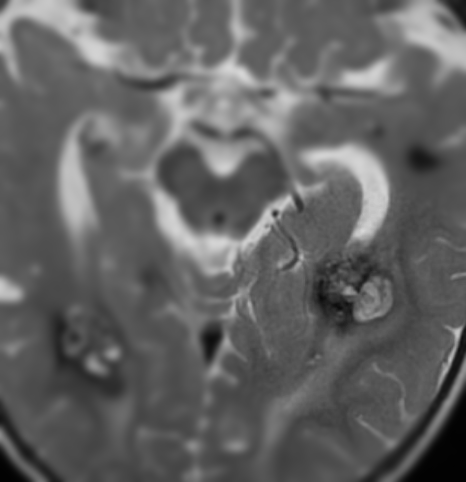

The Río Hortega Neurovascular Unit is a group of professionals with experience in the diagnosis and treatment of neurovascular pathology by open and endovascular techniques.

We have built a multidisciplinary team focused on the diagnosis and treatment of cerebral and spinal vascular disease that has extensive experience and a highly qualified team of professionals.